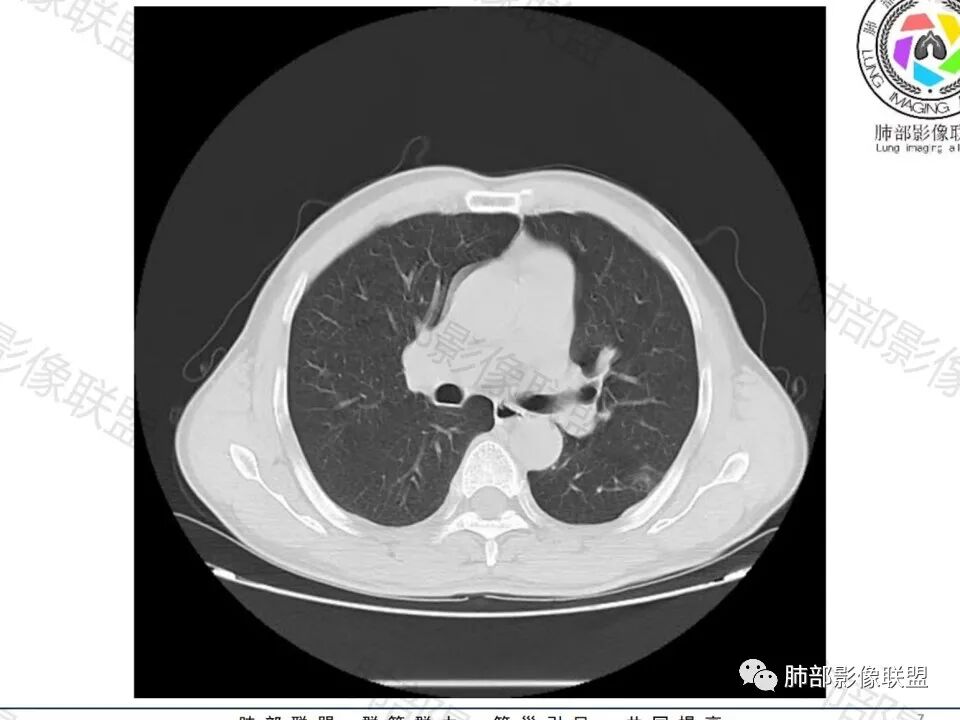

老年男性,左肺下叶背段胸膜下孤立结节,整体圆顿,周围有晕,晕中毛刺,似乎支持隐球,但边缘有一囊腔,恶性不能除外!等答案!

左下肺、右中肺均有结节,左下肺病灶比较鼓,边缘有晕,血管弯,持续性强化,考虑腺癌可能,鉴别两处病灶如果一元论,肉芽肿炎 (隐球)

图做的真漂亮!老年男性,双肺多发结节,最大者位于左肺下叶胸膜下,周围有晕,晕中毛刺,边缘有一囊腔,胸膜牵拉,持续强化,考虑隐球,鉴别腺癌。

老年男性,左肺下叶背段胸膜下结节,边缘毛刺,血管进入,斜裂有牵拉,局部胸膜糊墙,周围有晕,但有一囊腔,首先考虑腺癌,但是右肺中叶及左肺下叶还有其他结节,鉴别隐球菌

病史:男,60岁,体检左下肺结节,肿标阴性;

影像:轻微肺气肿,可能抽烟;旁边有个卫星灶4-5个,厚层无血管弯,薄层叶间裂轻度增厚,有囊腔,内侧有一个微血管,弯,另有两个微血管直,膨隆,增强血管不弯,糊墙,好像边界有些模糊,17-47-47,冠位轻度叶间裂弯。

诊断:警惕良性,隐球菌感染?

鉴别:腺癌,无磨玻璃,模糊?糊墙;纵膈窗太光滑,胸膜面广;不膨隆。支持点,薄层毛刺,强化。